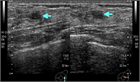

1. 30~40歳代の成熟期女性に好発する、硬結・腫瘤、疼痛、乳頭異常分泌などの症状を呈する乳腺の良性疾患である。